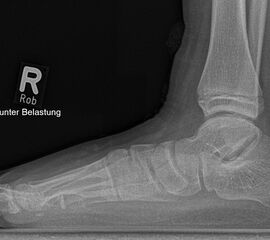

Diagnostisches Vorgehen

Damit die minimalinvasive Fußchirurgie zur Korrektur kindlicher oder jugendlicher Fußdeformitäten erfolgreich angewendet werden kann, erfordert die präoperative Diagnostik Röntgenbilder in drei Ebenen am stehenden Fuß. Röntgenbilder ohne Belastung des Fußes sind nicht zielführend. Im Fall von schweren Rückfußdeformitäten wird das obere Sprunggelenk in die radiologische Diagnostik mit einbezogen in Kombination mit der Rückfußaufnahme unter Belastung („Saltzman View“). Das OSG wird in zwei Ebenen geröntgt. Die streng seitliche Aufnahme des OSG kann bei den komplexen Fußdeformitäten mit der seitlichen Aufnahme des Fußes unter Belastung kombiniert werden. Das reduziert die diagnostische Strahlenbelastung der Kinder.

Indikationen für die beschriebenen Röntgenaufnahmen sind Klumpfußdeformitäten zur Beurteilung eines „flat top talus“ oder neurologische Grunderkrankungen mit varischer Fersenstellung wie zum Beispiel bei HSMN (Hereditäre Sensorische Motorische Neuropathie).